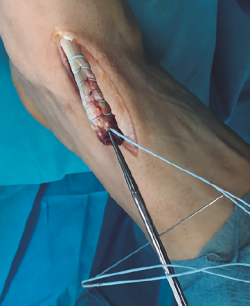

Figura 4. Preparación de túnel óseo en cuña medial con broca de 4,5 mm y colocación de los hilos en la placa metálica de 4 × 12 mm.

Figura 5. Inserción de la placa metálica a través del túnel óseo.

Se realiza túnel con broca de 4,5 mm al nivel de la cortical dorsal de la cuña medial con oblicuidad de proximal a distal hasta llegar a la cortical plantar (Figura 4). Posteriormente, se ensancha el mismo al nivel de la primera cortical según el diámetro del tendón tibial anterior, utilizando una pinza gubia o un avellanador.

Figura 6. Tracción de los hilos para deslizar el tendón tibial anterior en el túnel óseo.

Se procede a la introducción de la placa al nivel del túnel transóseo hasta empujarla fuera de la cortical plantar (Figura 5). Posteriormente, se introduce el tendón en el túnel de la cuña mediante la tracción de los hilos (Figura 6). En este paso resulta útil en ocasiones embocar con ayuda de un mosquito el tendón a la entrada del túnel óseo.

Figura 7. Anudado con ayuda de un empujahilos.

Finalmente, se realiza el anudado de la sutura sobre el sistema de fijación con ayuda de un empujanudos (Figura 7).